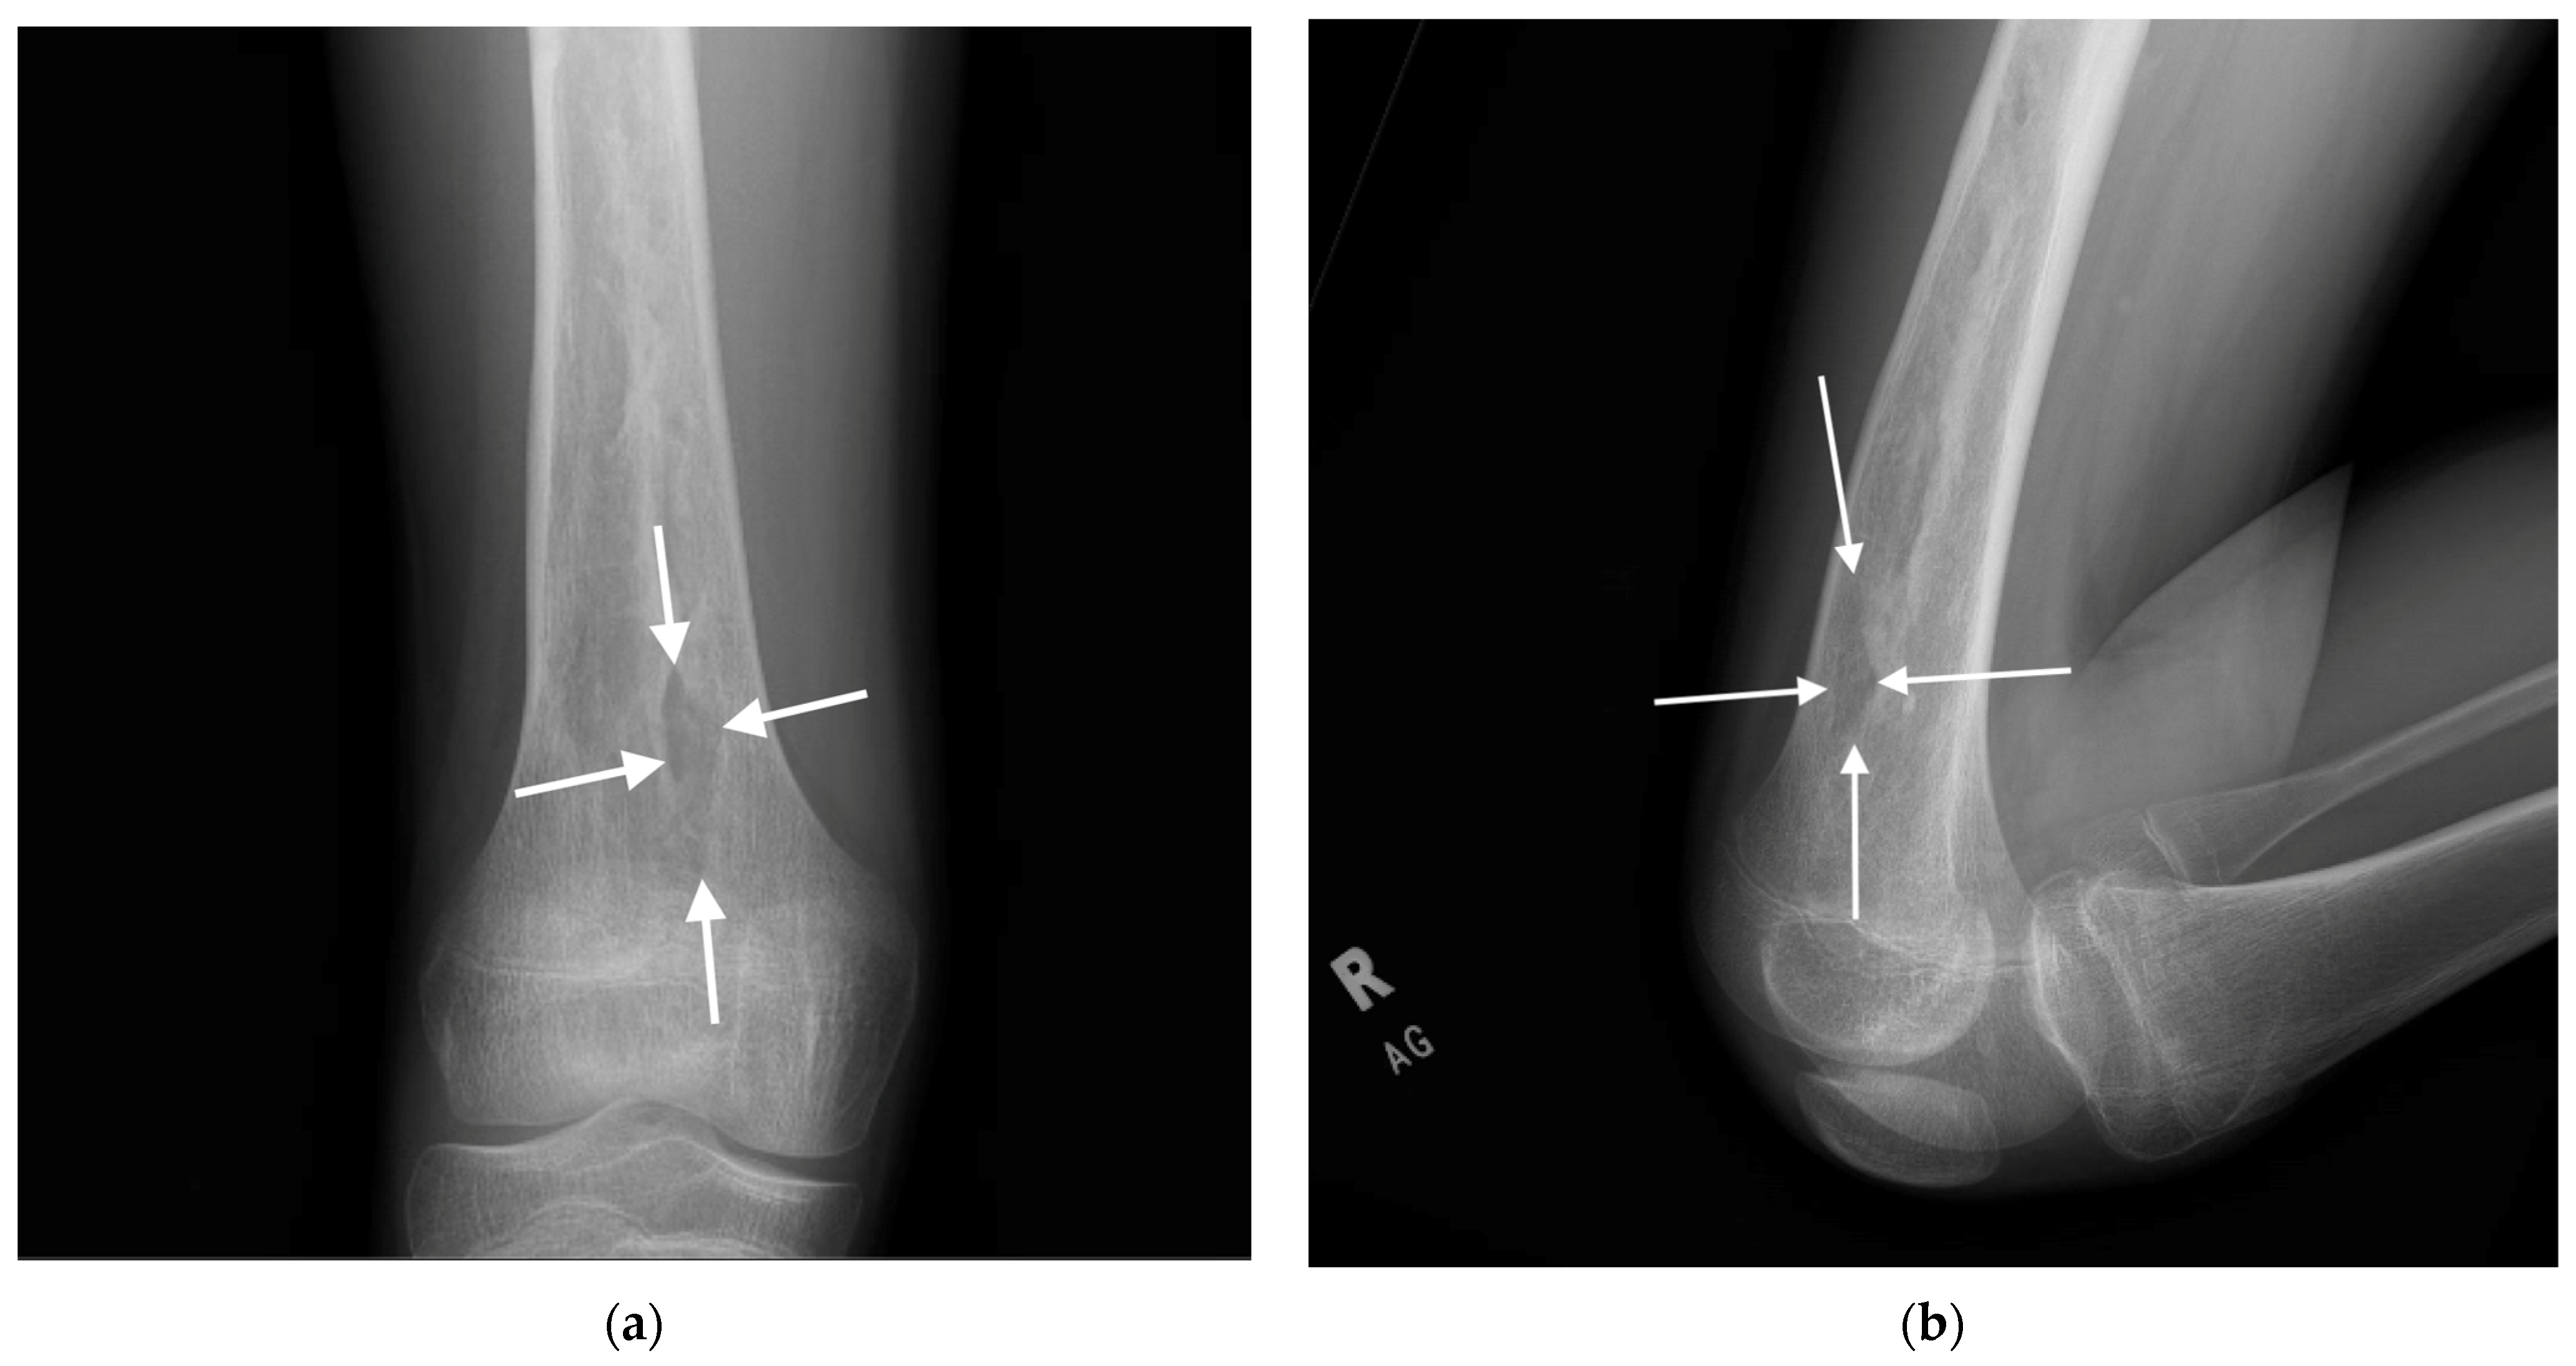

| 3 | 14 | M | 14.95 | Chronic multifocal (autoimmune) osteomyelitis, subperiosteal abscess, Brodie’s abscess | Disease-modifying rheumatologics | Brodie’s abscess, right femur I&D, subperiosteal abscess biopsy, right femoral IM antibiotic nail | Retained hardware |

| 3 | Femur | R | Irrigation and debridement | None | Greater trochanter | No | 14 mm | 12 mm | 10.5 mm | Continuous | Continuous | N/A |

| 3 | Anterior cortical breach | Intraop | Fluoroscopy | Grade I | Nothing | No long-term sequelae | 670 days | No | None |